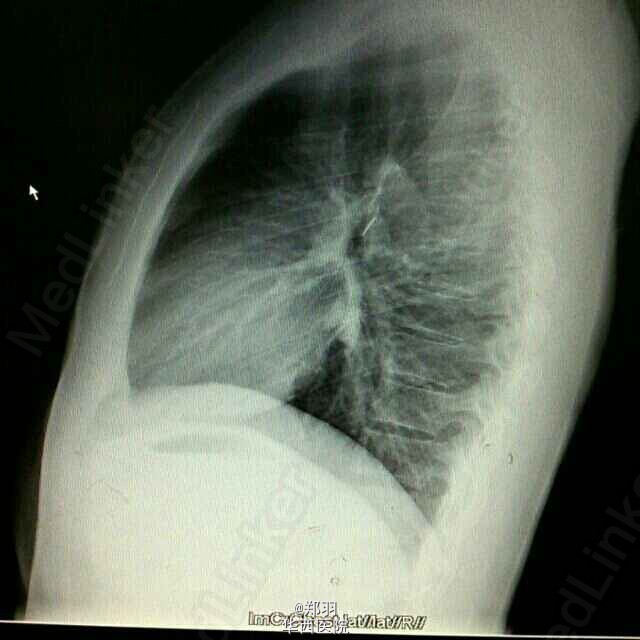

患者,男,24岁,体检发现左肺上叶异物1+月。无任何其他不适。

胸部平片及胸部CT平扫提示左肺上叶有一细条状金属异物。纤支镜提示左肺支气管分叉处有瘢痕,为金属异物从后背刺入肺内,并深入支气管,因为术中发现后方胸膜有粘连。